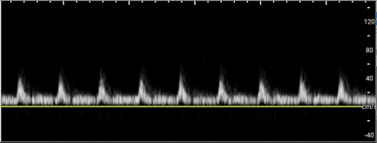

• A healthy testicle should appear oval-shaped and roughly 3–5 cm in length, by 2–3 cm in width depending on the age. Testicles have a homogeneous appearance with a medium-level echogenicity (like other solid organs). They are smooth and uniform throughout when healthy. Start by fanning through the testicle in transverse and longitudinal orientations to get a general assessment. When applying color Doppler to a well perfused testicle, there should be uniform, low velocity arterial and venous blood flow throughout the parenchyma. Vessels may appear pinpoint, linear or branching. Using spectral Doppler, the velocity of specific vessels can be measured. Arterial flow will appear as a brisk upstroke and sharp downstroke reflecting the cardiac cycle. Venous flow has a continuous velocity with less variation, often described as a “venous hum” (Images 6 and 7).7

Torsion - image 6.pngImage 6. Arterial flow on Spectral Doppler.

Torsion - image 7.pngImage 7. Venous flow on Spectral Doppler.